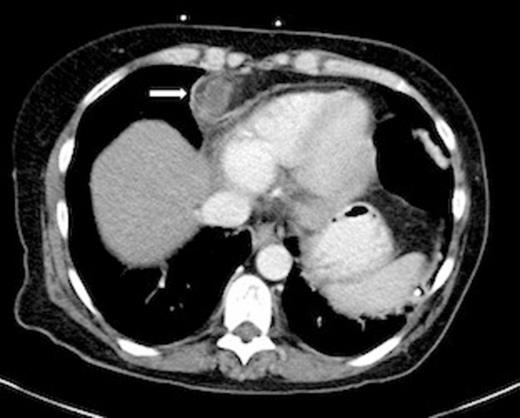

A 54-year-old female with a history significant for alcohol abuse, surgical correction of annular pancreas 20 years ago and chronic pancreatitis presented to a rural emergency department with a 1-week history of worsening severe epigastric pain, nausea and vomiting. She was in baseline health until 2 months prior when she first noticed episodic epigastric pain that was stabbing in nature. The patient was transferred to our institution for surgical evaluation based on an external department CT raising concern of possible diaphragmatic herniation versus fluid collection. Re-scan of the abdomen confirmed a fluid collection of 8-10 cm in the extra-peritoneal space of the intra-abdominal wall, extending superiorly to the anterior mediastinum. Subsequent laparoscopy revealed dense omental adhesions encapsulating an abscess cavity, which tracked into the inferior mediastinum. Purulent material was evacuated, fluid was sampled for bacterial culture and a Blake drain was placed. There was no evidence of existing mesh, intestinal fistula or enterotomy. The precise etiology of the abscess remains unclear. The patient was afebrile without leukocytosis throughout the hospital course and was discharged with clinic follow-up after 3 days of post-operative evaluation. At the one-month post-operative clinic visit, symptoms had resolved.

Axial CT Chest showing anterior inferior mediastinal abscess (Arrow).